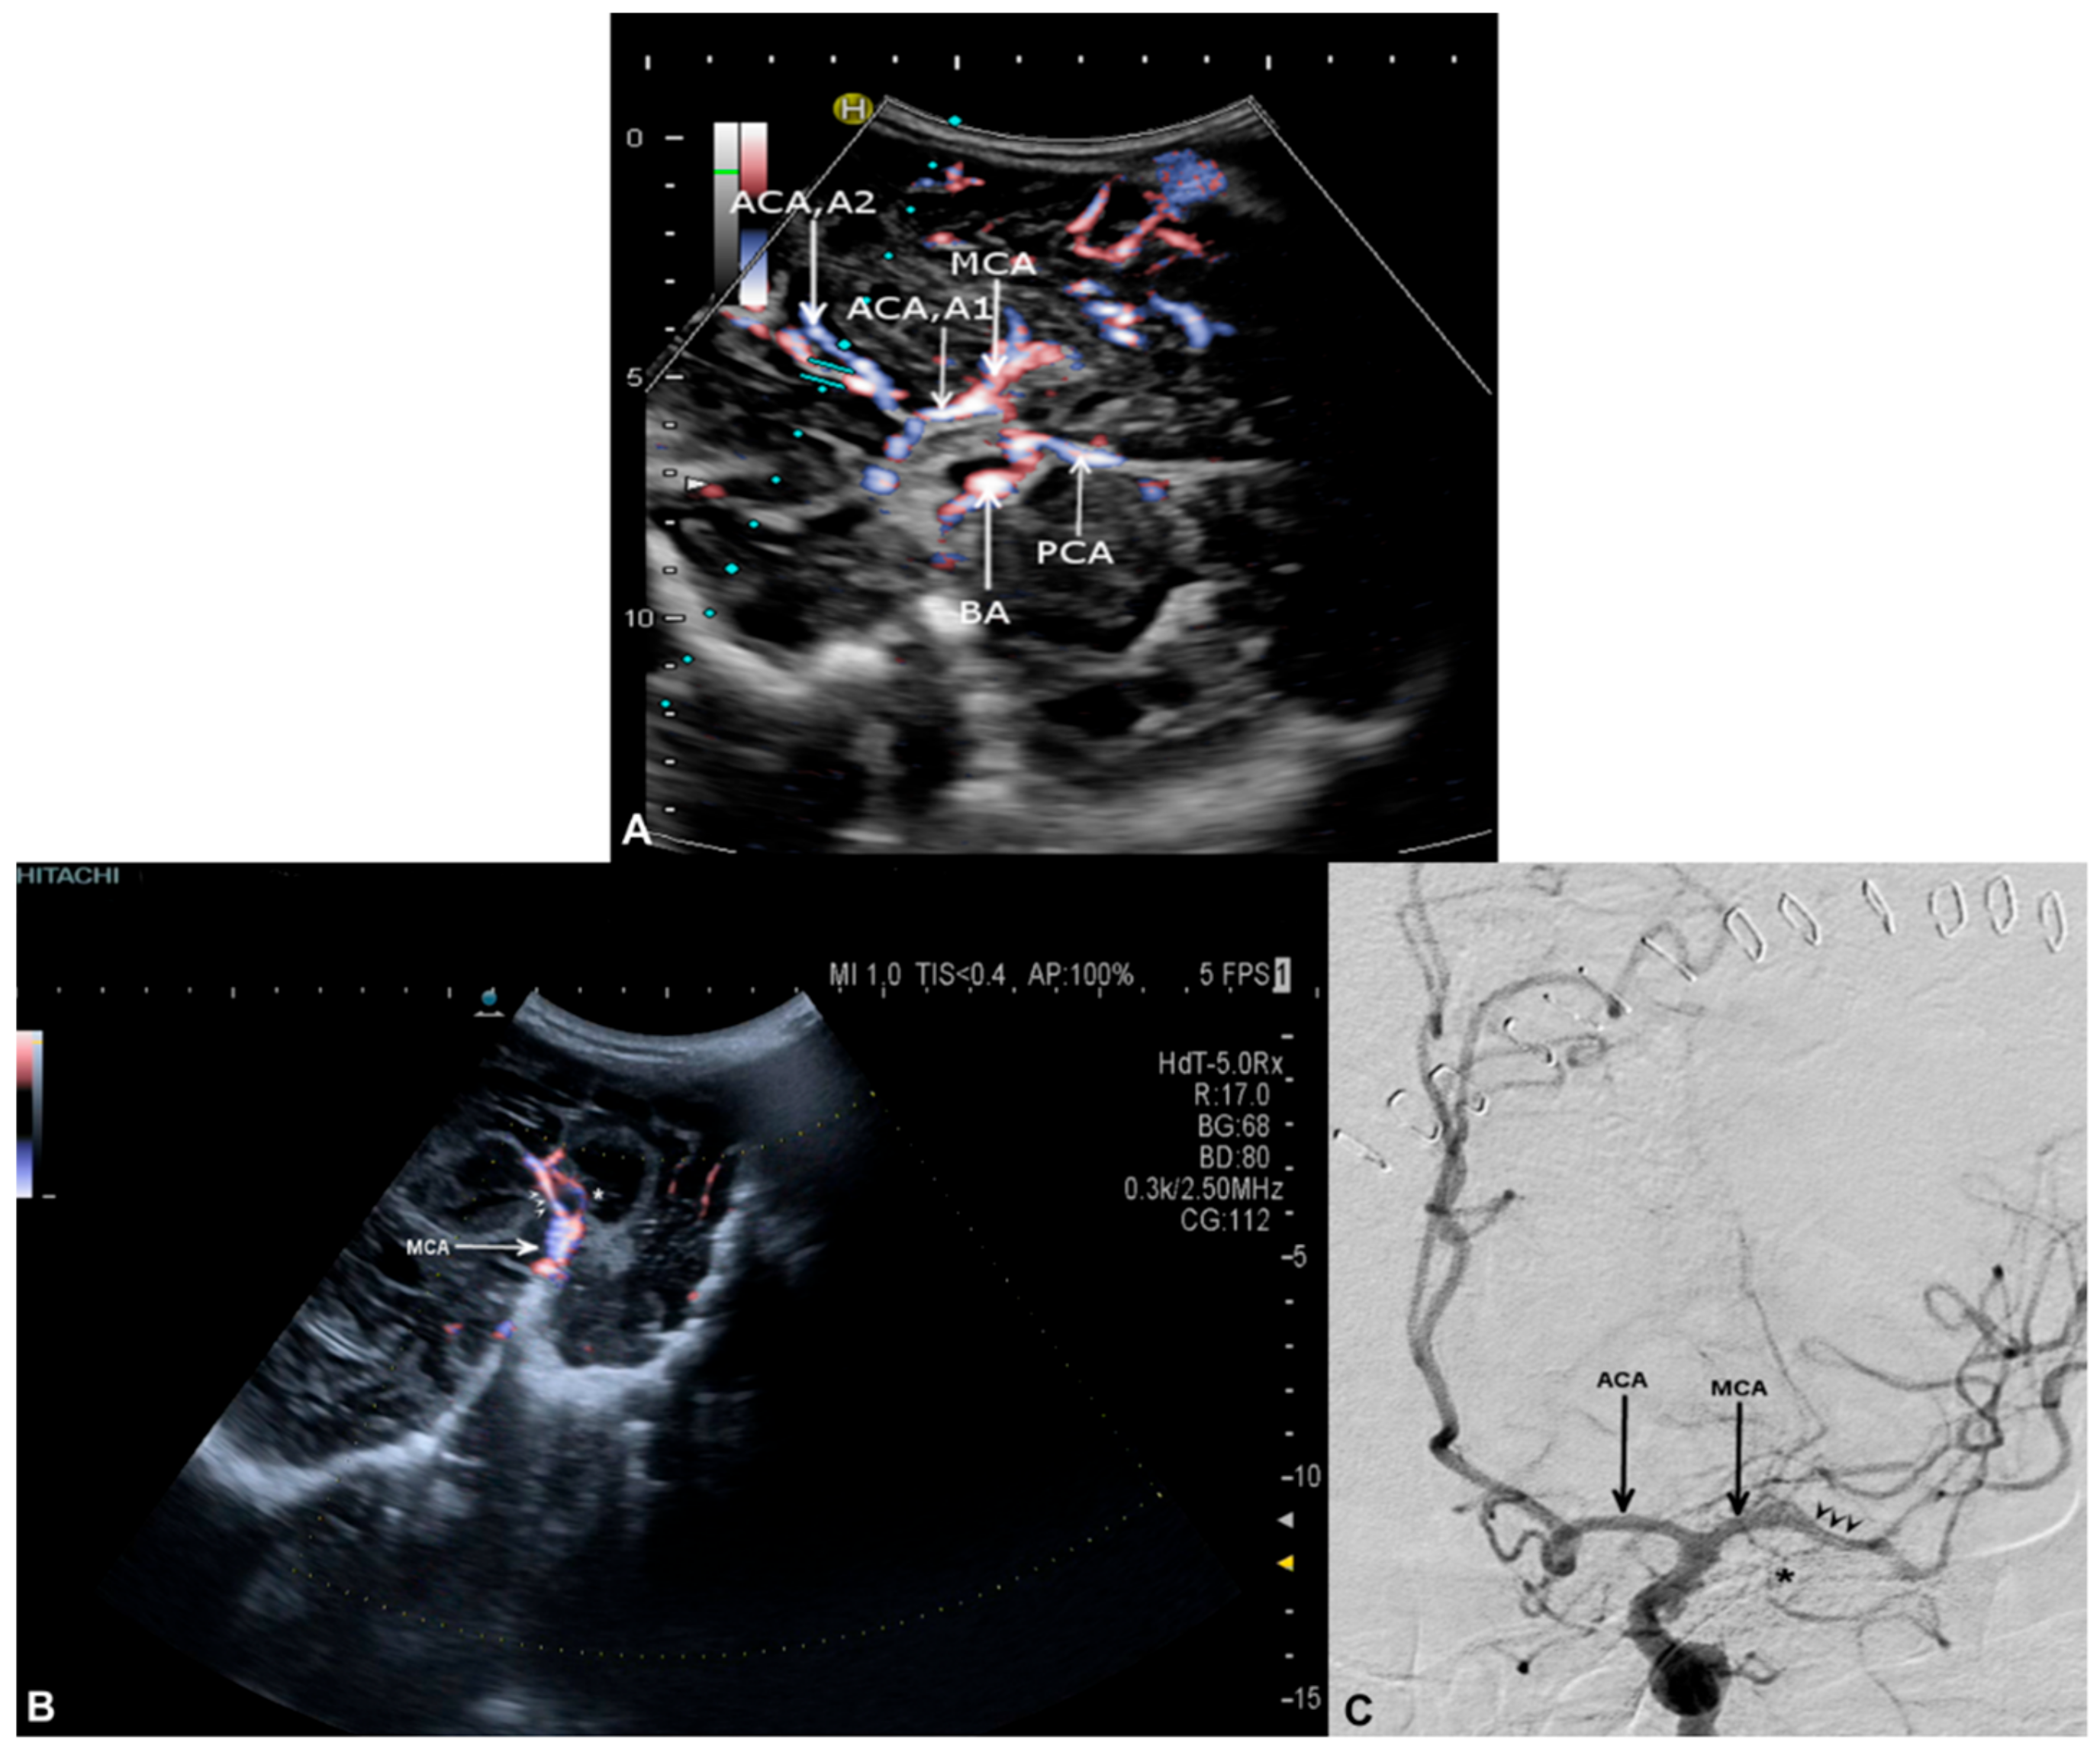

3.2. Cerebral Arteries